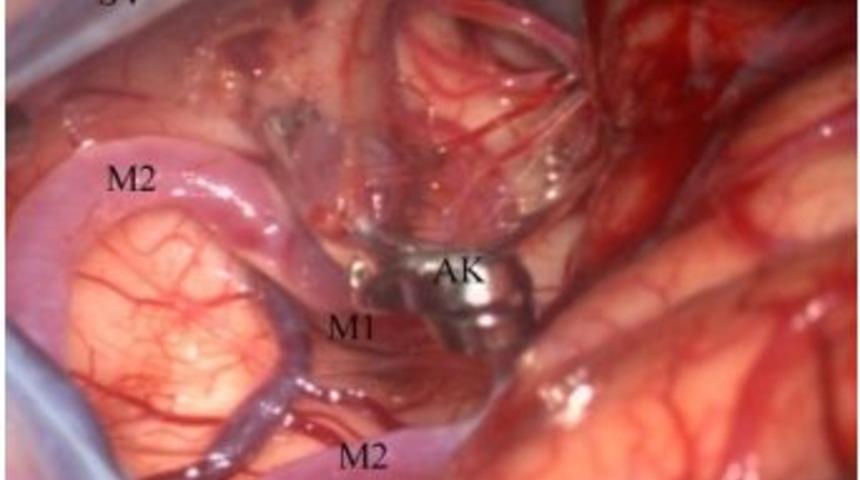

Ondokuz Mayıs Üniversitesi (OMÜ) Tıp Fakültesi Beyin Cerrahisi Ana Bilim Dalı Başkanı Prof. Dr. Cengiz Çokluk, sigara tüketilmesinin beyin damarlarında baloncuk gelişmesini kolaylaştırdığını söyledi.Prof. Dr. Cengiz Çokluk, sigara içilmesi ve hipertansiyon beyin anevrizmalarının (baloncuk) gelişimindeki etkilerini anlattı. Prof. Dr. Çokluk, “Beyin damarlarında baloncuk gelişimi yaklaşık olarak toplumun yüzde 2’sini ilgilendiren bir sağlık sorunudur. Bireysel farklılıkların yanında genetik, bölgesel, ırksal ve çevresel faktörler baloncuk gelişiminde etkili olduğu gibi kanama olayında da etkilidir. Beyin damarlarında görülen bu balonlaşmanın tıp literatüründeki ismi ‘anevrizma’dır. Bu balonlaşmalar her yaşta görülmekle birlikte en çok 40-60 yaşları arasında şikayet oluşturmaya başlarlar. Kadın ve erkekler arasındaki görülme sıklığına baktığımızda kadınlarda erkeklere oranla daha sık görüldüğü ortaya çıkar. Bugüne kadar yapılan tüm bilimsel çalışmalar genetik ve çevresel faktörler üzerinde yoğunlaşmıştır. Beyin damarlarında baloncuk gelişimi üzerinde doğumsal ve genetik faktörlerin etkili olduğu bilgisi tıp literatürüne yerleşmiş, ispatlanmış doğrulardan birisidir. Bununla birlikte asıl önemli olan soru çevresel faktörler olarak adlandırabileceğimiz faktörlerin ne derece beyin damarlarında baloncuk gelişiminde etkili olduğudur. Burada çevresel faktörler içerisinde sayılabilecek sigara tüketilmesinin beyinde baloncuk gelişmesini nasıl kolaylaştırdığı konusunda kısa bilgiler verilecektir” dedi.İnsan beyninin kişisel ve toplumsal tüm bilginin üretildiği, sınıflandırıldığı, saklandığı ve çeşitlendirildiği organik bir bilgisayar olduğunu belirten Prof. Dr. Cengiz Çokluk, “Tüm bu işlemlerin sorunsuz yapılabilmesi için glukoz adını verdiğimiz organik bir şeker türüne ihtiyaç duyar. Vücudumuzda bulunan diğer hücreler enerji kaynağı olarak protein, yağ ve karbonhidratları kullanabilmekle birlikte beynimiz sadece saf ve temiz bir yakıt (yani enerji kaynağı) olan glukozu kullanır. Glukozun belli bir oranda beyin dokusuna sürekli gelebilmesi için kan akımının sürekli olması gerekmektedir. İnsan beyni kalpten pompalanan kanın yaklaşık olarak yüzde 20’sini kullanır. Bunun beyin dokusunun hacmi ve vücutta kapladığı yerle kıyaslandığında muazzam bir büyüklüğe sahip olduğu anlaşılacaktır. Beyin dokusuna bu kanın iletilmesinde beyin damarları görev almaktadır. Konumuz zaten bu kadar yoğun bir kan taşıma işlemini yürüten beyin damarlarının baloncuk (anevrizma) adı verilen bir hastalığıdır. Beyin damarlarının kan taşıma fonksiyonunu göremediği durumda beyinin o bölgesinde beslenme yetersizliği ortaya çıkar ki bu olaya inme (iskemi/infakt) adını vermekteyiz” diye konuştu.“Elimizi bileğimizdeki radial arter dediğimiz nabzımızın üzerine koyduğumuzda kan akımının nabız adı verdiğimiz kalbimizin atımlarını yansıtan elastik, inişleri ve çıkışları olan bir yapısının olduğunu görürüz” diyen Çokluk, “Bu atımlar aynı şekilde beyindeki damarlarda da mevcuttur. Kan damarlarına bu özelliği sağlayan kan damarlarının duvarındaki özel yapıdır. Bu özel yapıyı oluşturan temel unsurlar iki gruba ayrılabilir. Bunlardan birisi damar duvarı kas dokusudur. İkinci ana unsur ise liflerdir. Bu lifler oldukça önemlidir. Üç çeşit lif vardır bunlar kollajen, elastik ve laminin lifleridir. Bu lifler damar duvarının sağlamlığını sağlayan temel unsurlardır. Bu lifler içerisinde damar duvarının elastikliğini ve sağlamlığını sağlayan elastik lifler son derece önemlidir. Damar duvarındaki elastik lifler kalp atışlarıyla uyumlu olarak sıkılaşır ve gevrekleşir. Bunu kendi içerisinde uzayıp kısalarak yapar. Bunu sağlayan kendi içerisindeki mikro bağlardır. Bu küçük bağcıkların yapısı sigara tarafından güçsüzleştirilebilir, bu güçsüzlük hipertansiyon ile birleştiğinde damarların kıvrım yerlerinde baloncuklaşmalar başlar ve bunlar büyüyerek gerçek bir baloncuğa yani anevrizmaya döner. Dolayısıyla sigara içer bir kişide kan damarlarının elastikliğinde sorun yaşanmaktadır. Uzun dönem sigara içen bir insanın cilt dokusuna bile bakıldığında süreç içerisinde vücut dokusunun ne denli elastikliğini kaybettiği anlaşılacaktır” şeklinde konuştu.Prof. Dr. Cengiz Çokluk şöyle devam etti: “Elastikliği azalmış damar duvarının hipertansiyon gibi basınç artışına karşı direncinin sigara kullanmayan bir kişiyle kıyasladığımızda azalmış olacağı şüphe kaldırmaz bir gerçektir. Sonuç olarak damar duvarında gelişen bu baloncuklar giderek büyür ve duvarı giderek güçsüzleşir. Baloncuğun duvarı yırtılır ve beyin kanaması dediğimiz durum ortaya çıkar. Damar duvarından beyine sızan kan miktarı az (yani sızma şeklinde) ise hastaların tarifiyle ‘daha önceden hissetmediğim ölçüde şiddetli bir baş ağrısı’ şeklinde tanımlanmaktadır. Kanama anında hastalar genellikle bilinçlerini kaybederler. Bu dönemde yakınları tarafından hastaneye getirilirler. Hastalar hastaneye getirildiklerinde beyin damarlarının görüntülenmesi için beyin damar anjiografisinin yapılması gereklidir. Bu amaçla bilgisayarlı tomografik anjiografi, manyetik rezonans görüntüleme anjiografi veya dijital anjiografi denen beyin damar anjiografileri yapılabilir. Bu anjiografiden sonra hastaların tedavisinde endovasküler veya mikrocerrahi ile tedavi yöntemlerinden birisine karar verilerek baloncuğun tedavisi yoluna gidilir. Baloncuk tedavisinin birincil amacı baloncuğun tekrar kanamasının önlenmesidir. Çünkü tekrar kanama ölümle sonuçlanabilir. Beyin anevrizmalarının tedavisinde yaygın olarak kullanılan mikrocerrahi teknikler özellikle 1970’li yıllardan sonra geliştirilmiştir. Anevrizmalara yönelik mikrocerrahi yöntemlerin geliştirilmesinde o yıllarda Zürih Üniversitesi’nde bulunan M.G. Yaşargil hocanın büyük katkısı vardır. Yaşargil’in Mikronörocerrahi adlı kitabı mikrocerrahinin temel prensiplerini detaylarıyla anlatmaktadır. Anevrizmaların cerrahi tedavisinde yaygın olarak kullanılan mikrocerrahi yöntemler için hastanın ameliyata hazırlık süreci vardır. Cerrahi tedavisinde uygulanan anestezi yöntemleri diğer cerrahi dallarda uygulanan anestezi yöntemlerinden biraz farklıdır. Ameliyat çıplak gözle değil de ameliyat mikroskobu kullanılarak yapılmaktadır. Ameliyat sırasında baloncuğa ulaşılmakta ve baloncuğun boynuna klips adı verilen bir cihaz yerleştirilmektedir. Daha sonra hastalar servise alınmakta ve tedavileri burada devam ettirilmektedir. Beyin anevrizmalarının tedavisi günümüzde her ne kadar ilerlese de hastalığın oluşmasında suçlanan sigaradan uzak durulması, özellikle hipertansiyonu olan hastaların sigara konusuna önem vermeleri sağlık açısından son derece önemlidir.”